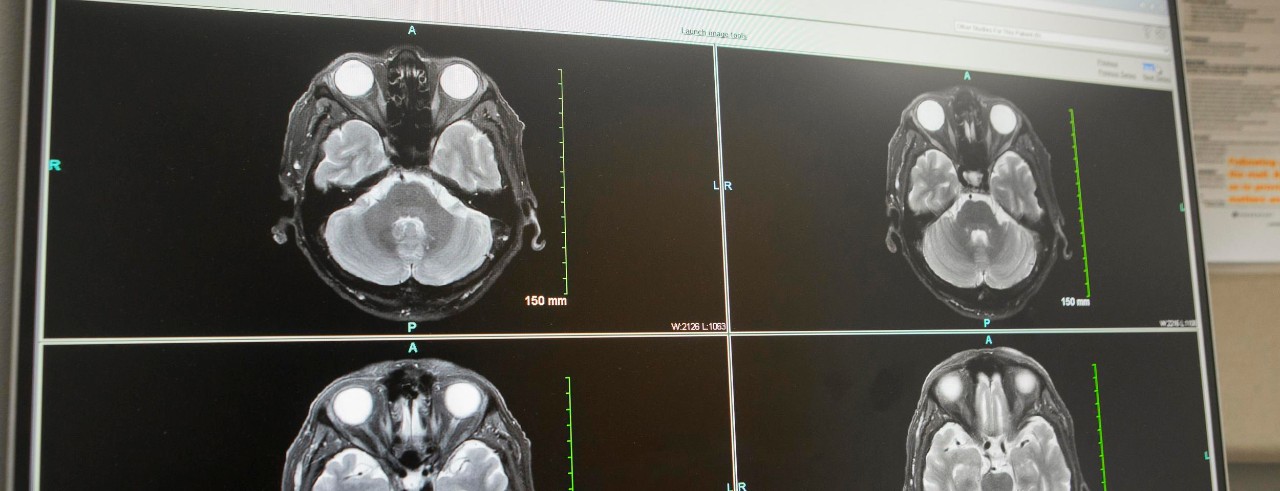

Results of a new international trial showed performing endovascular thrombectomy in stroke patients with a large ischemic core is beneficial.

Endovascular thrombectomy is a minimally invasive procedure for acute ischemic stroke patients that uses a catheter to remove a blood clot from a blood vessel in the brain, which restores blood flow. Patients with strokes with a large ischemic core were previously not considered candidates for thrombectomies because of concerns of an increased risk of hemorrhage, disability and death.

The results of the trial "will change practice and extend endovascular therapy to more patients with severe strokes," Broderick continued. However, he noted imaging will still be necessary to exclude a certain subset of patients with large ischemic core who were not included in the trials.

"These are patients who have very large areas of clear hypodensity on the baseline image (brain already dying or dead)," Broderick said. "These patients do not benefit from reperfusion with lytic drugs or endovascular therapy."

Featured photo at top of brain scans. Photo/Joseph Fuqua II/UC Marketing + Brand.